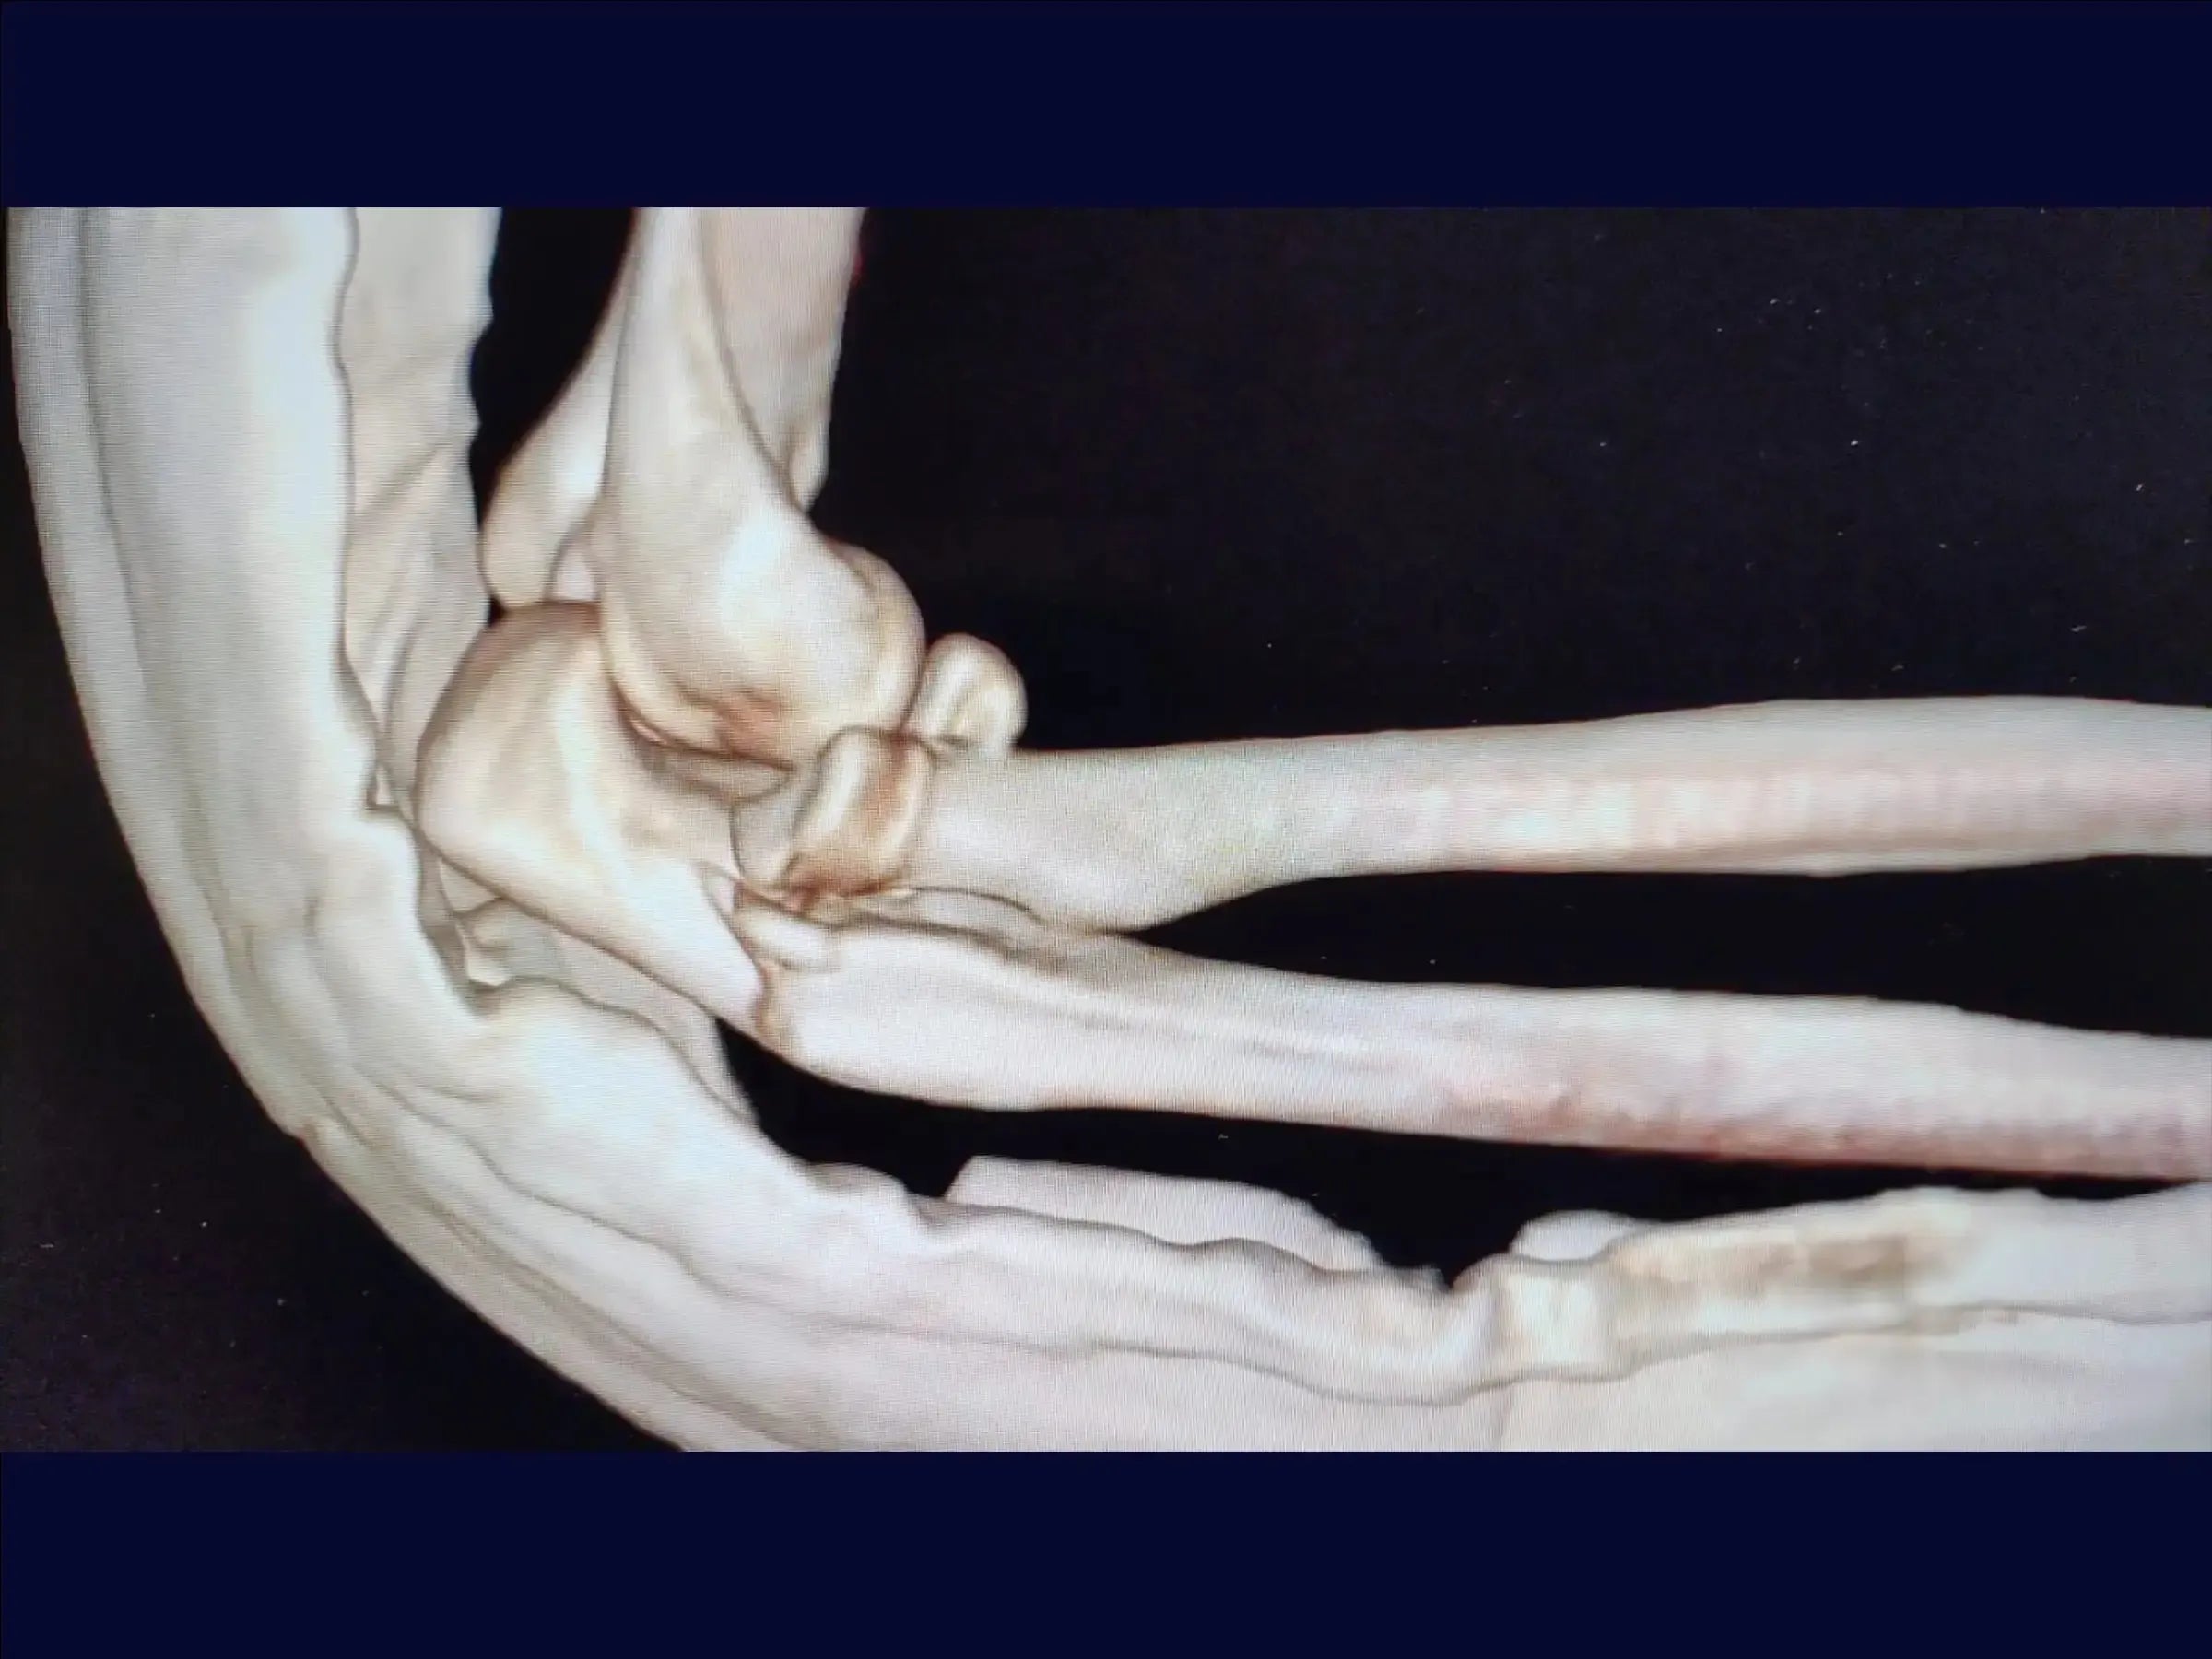

Fractura metafisaria del cúbito proximal con luxación y fractura de la cabeza radial (variante de Monteggia)

Mejore sus habilidades en el tratamiento de una de las lesiones de codo más complejas: la fractura metafisaria del cúbito proximal asociada a la luxación posterior y la fractura de la cabeza radial, conocida como variante de Monteggia . Esta formación abarca la reducción anatómica del cúbito y la cabeza radial, la fijación con placas y tornillos, y la reinserción de estructuras ligamentosas, con el objetivo de restaurar la estabilidad articular y permitir la movilidad temprana del codo, minimizando el traumatismo tisular y optimizando el resultado estético.

- Tratamiento quirúrgico de la fractura metafisaria del cúbito proximal con luxación posterior y fractura de la cabeza radial ( variante de Monteggia ).

- Reducción anatómica del cúbito y la cabeza radial.

- Acceso a la cabeza radial: Portal posterolateral a través del ancóneo, evitando múltiples planos. Ampliación con desinserción del ligamento colateral lateral y luxación controlada.